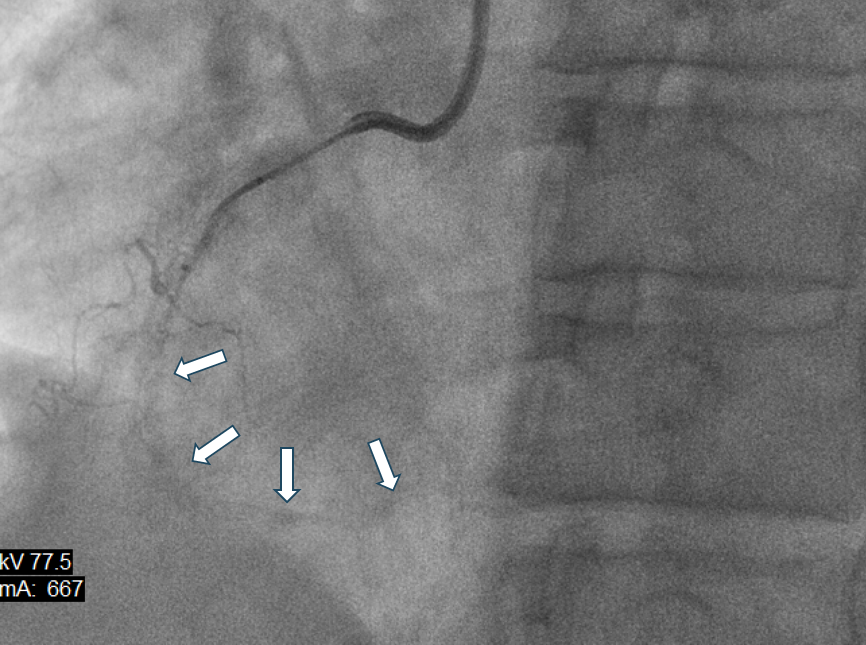

开通过程开始,右冠状动脉全段闭塞且全称弥漫钙化(箭头所指为闭塞血管段,但是由于明显钙化(石头),未用造影剂就已经可以看到血管轮廓)